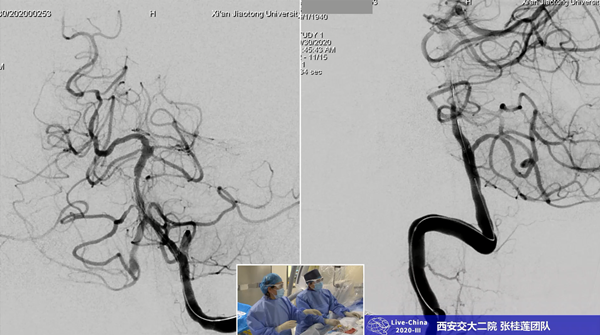

术前

此次手术演示直播,我院神经内科选择的手术是神经介入难度大、风险高的基底动脉狭窄支架成形术,而且患者系79岁高龄,合并高血压、糖尿病等多种并发症,更增加了手术的风险和难度。术前经过全科讨论,充分准备,对患者病情进行详细评估,尤其是做了我科在国内率先开展的椎基底动脉颅内段平行扫描的BPAS-MRl检查。张主任提前与麻醉科吕建瑞主任充分沟通,在影像科、麻醉科的支持下,由麻醉科赵红霞医师实施全麻,由张桂莲教授主刀,张茹副教授做学术导播全程讲解,展淑琴教授作为一助,张磊医生做二助,护士张倩和蒋鹏鹏辅助手术,范松华博士进行病例汇报。

术中北京天坛医院神经介入科莫大鹏教授、中国医科大学第四附属医院神内高连波教授通过远程直播平台实时点评,对此次直播的手术难度、技术细节等进行点评、交流。历经一个多小时,手术顺利完成,圆满取得预期效果。此次直播利用我院新引进的西门子双C臂血管造影机,充分展示了新型血管造影机在神经介入方面的优势,展示了我院神经内科规范、先进的介入治疗方式和技巧。